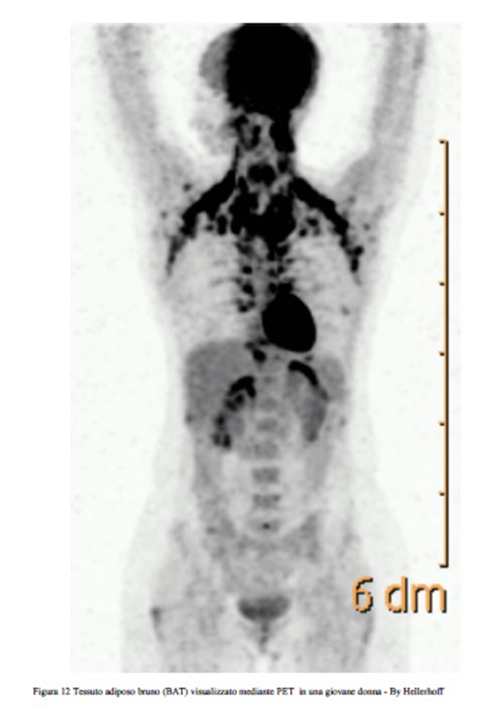

Il tessuto adiposo bruno (BAT) è particolarmente abbondante, oltre che negli animali che vanno in letargo, nei neonati dell’uomo e diminuisce con l’avanzare dell’età. Il BAT nell'uomo è localizzato principalmente in sede paracervicale, sopraclavicolare, interscapolare, perirenale (Figg. 11, 12).

In tali sedi i depositi del BAT hanno rapporti rilevanti con i vasi sanguigni che possono, così veicolare, tramite il flusso sanguigno il calore prodotto (Cold Induced Non Shivering Thermogenesis o NST) al resto dell’organismo.

Figura 12 Tessuto adiposo bruno (BAT) visualizzato mediante PET in una giovane donna - By Hellerhoff